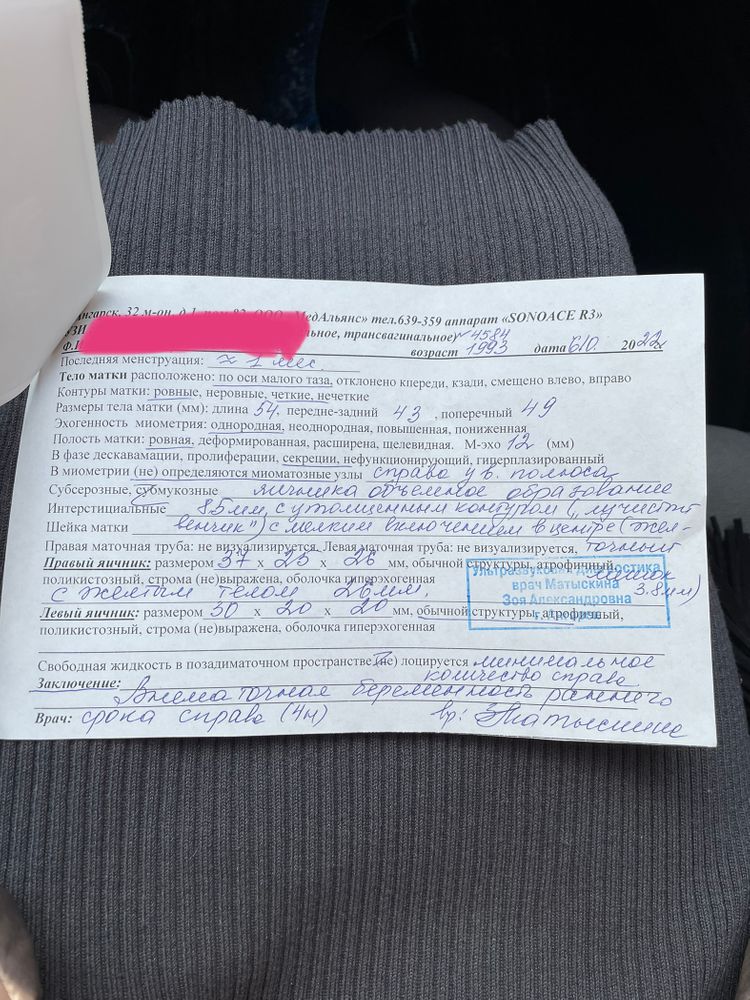

Девочки привет.. хочу рассказать историю со своей проблемой. 02.10.22 начались месячные ( как я думала). Приложение в котором я отслеживала цикл у меня сгрузилось, попытавшись загрузить его заново обнаружила что все данные о последних м пропали.. По итогу 02.10 приходят месячные, точнее какая то мазня не активная темно-коричневого цвета. Расцениваю это как начало, но проходит день, два, ничего не меняется. На третий день что то дернуло меня сделать тест, и какого было мое удивление когда я увидела две жирные яркие полоски… С утра проснулась, мазня как будто бы усилилась, я побежала срочно на узи, на узи мне сообщили что у меня внематочная, показали снимок и дали направление на стационар.. слезы, отчаяние, принятие…. Пишу своему врачу, описываю ситуацию, мой врач меня посылает на еще одно узи в другую клинику. Делаю повторное узи, ничего нет… показываю снимок первого узи, узист говорит что это не похоже совсем на внематочную, но так как есть диагноз от первого врача, все же советует мне лечь на стационар для наблюдения. Пишу опять своему врачу, врач направляет меня на ХГЧ. С утра бегу сдаю, на след день получаю результат 10460….. пишу врачу, отправила меня на повторную сдачу 10.10. и назначила утрожестан, мазня вроде прекратилась.Сейчас нахожусь в неведении что это может быть((( Болей как таковых нет, разве что может покалывать то справа то слева, и вечером немного тянет низ живота как при месячных.беременность первая и долгожданная.. очень много через что прошла.. у кого была подобная история, поделитесь пожалуйста…(